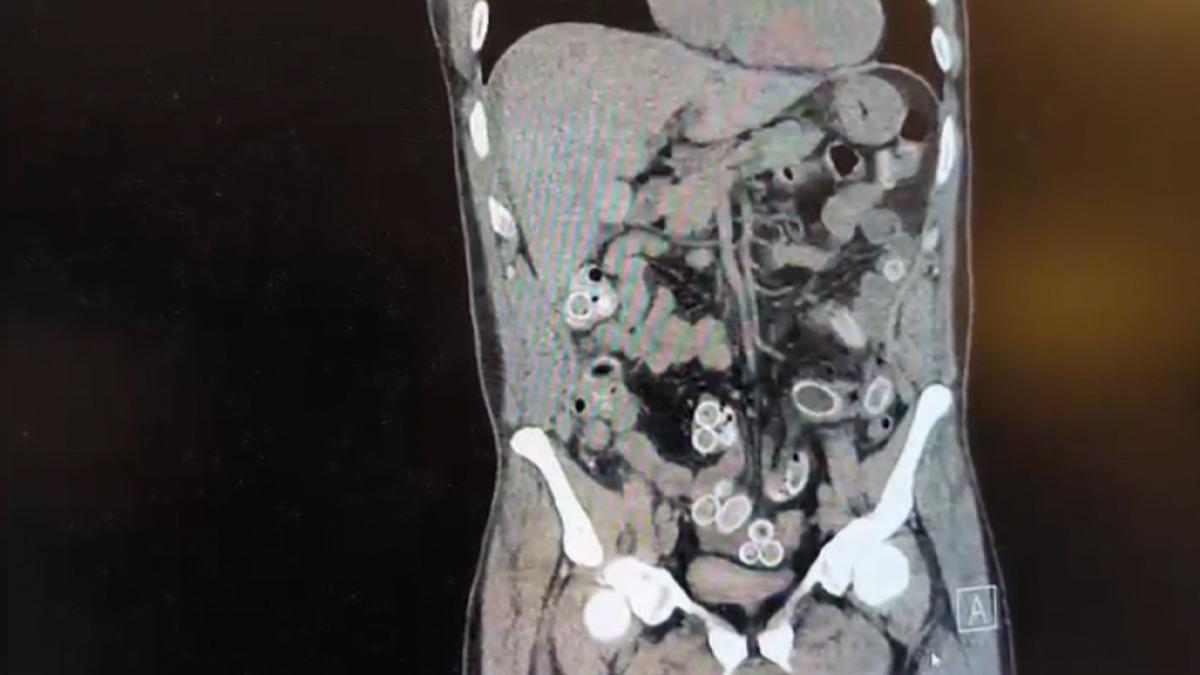

Beşiktaş’ta 3 bin kilometre uzaklıktaki Fas’tan uçakla Türkiye’ye gelen Cüneyt Ç. (52), 2 gün sonra mide ağrısı şikayetiyle hastaneye gitti. Tomografisi çekilen Cüneyt Ç.’nin mide ve bağırsaklarında yabancı madde bulunduğu tespit edildi. Hastane yetkililerinin bilgi vermesi üzerine Beşiktaş Asayiş Büro Amirliği ekipleri tarafından konuyla ilgili çalışma başlatıldı. Ameliyata alınan Cüneyt G.’nin mide ve bağırsaklarından kapsül halinde 49 adet esrar macunu çıkarıldı.